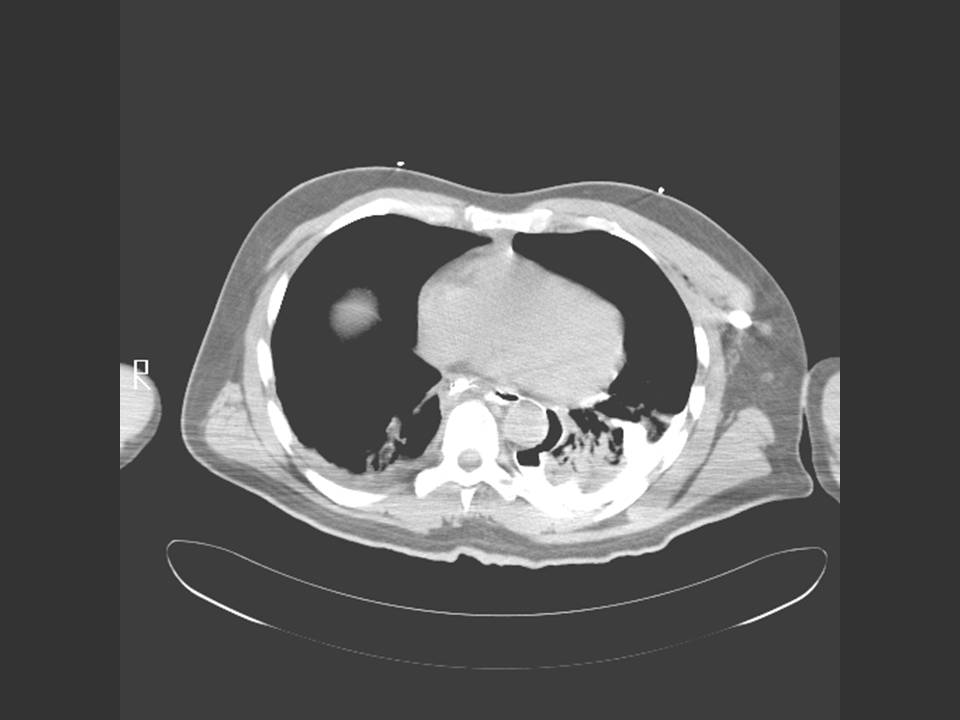

Chest CT is indicated if there is a high clinical suspicion of perforation but contrast esophagogram is negative. In addition, chest CT allows better delineation of the extent of mediastinal disease. Figure 4 shows leakage of contrast from the distal esophagus, across the mediastinum to the pleura.